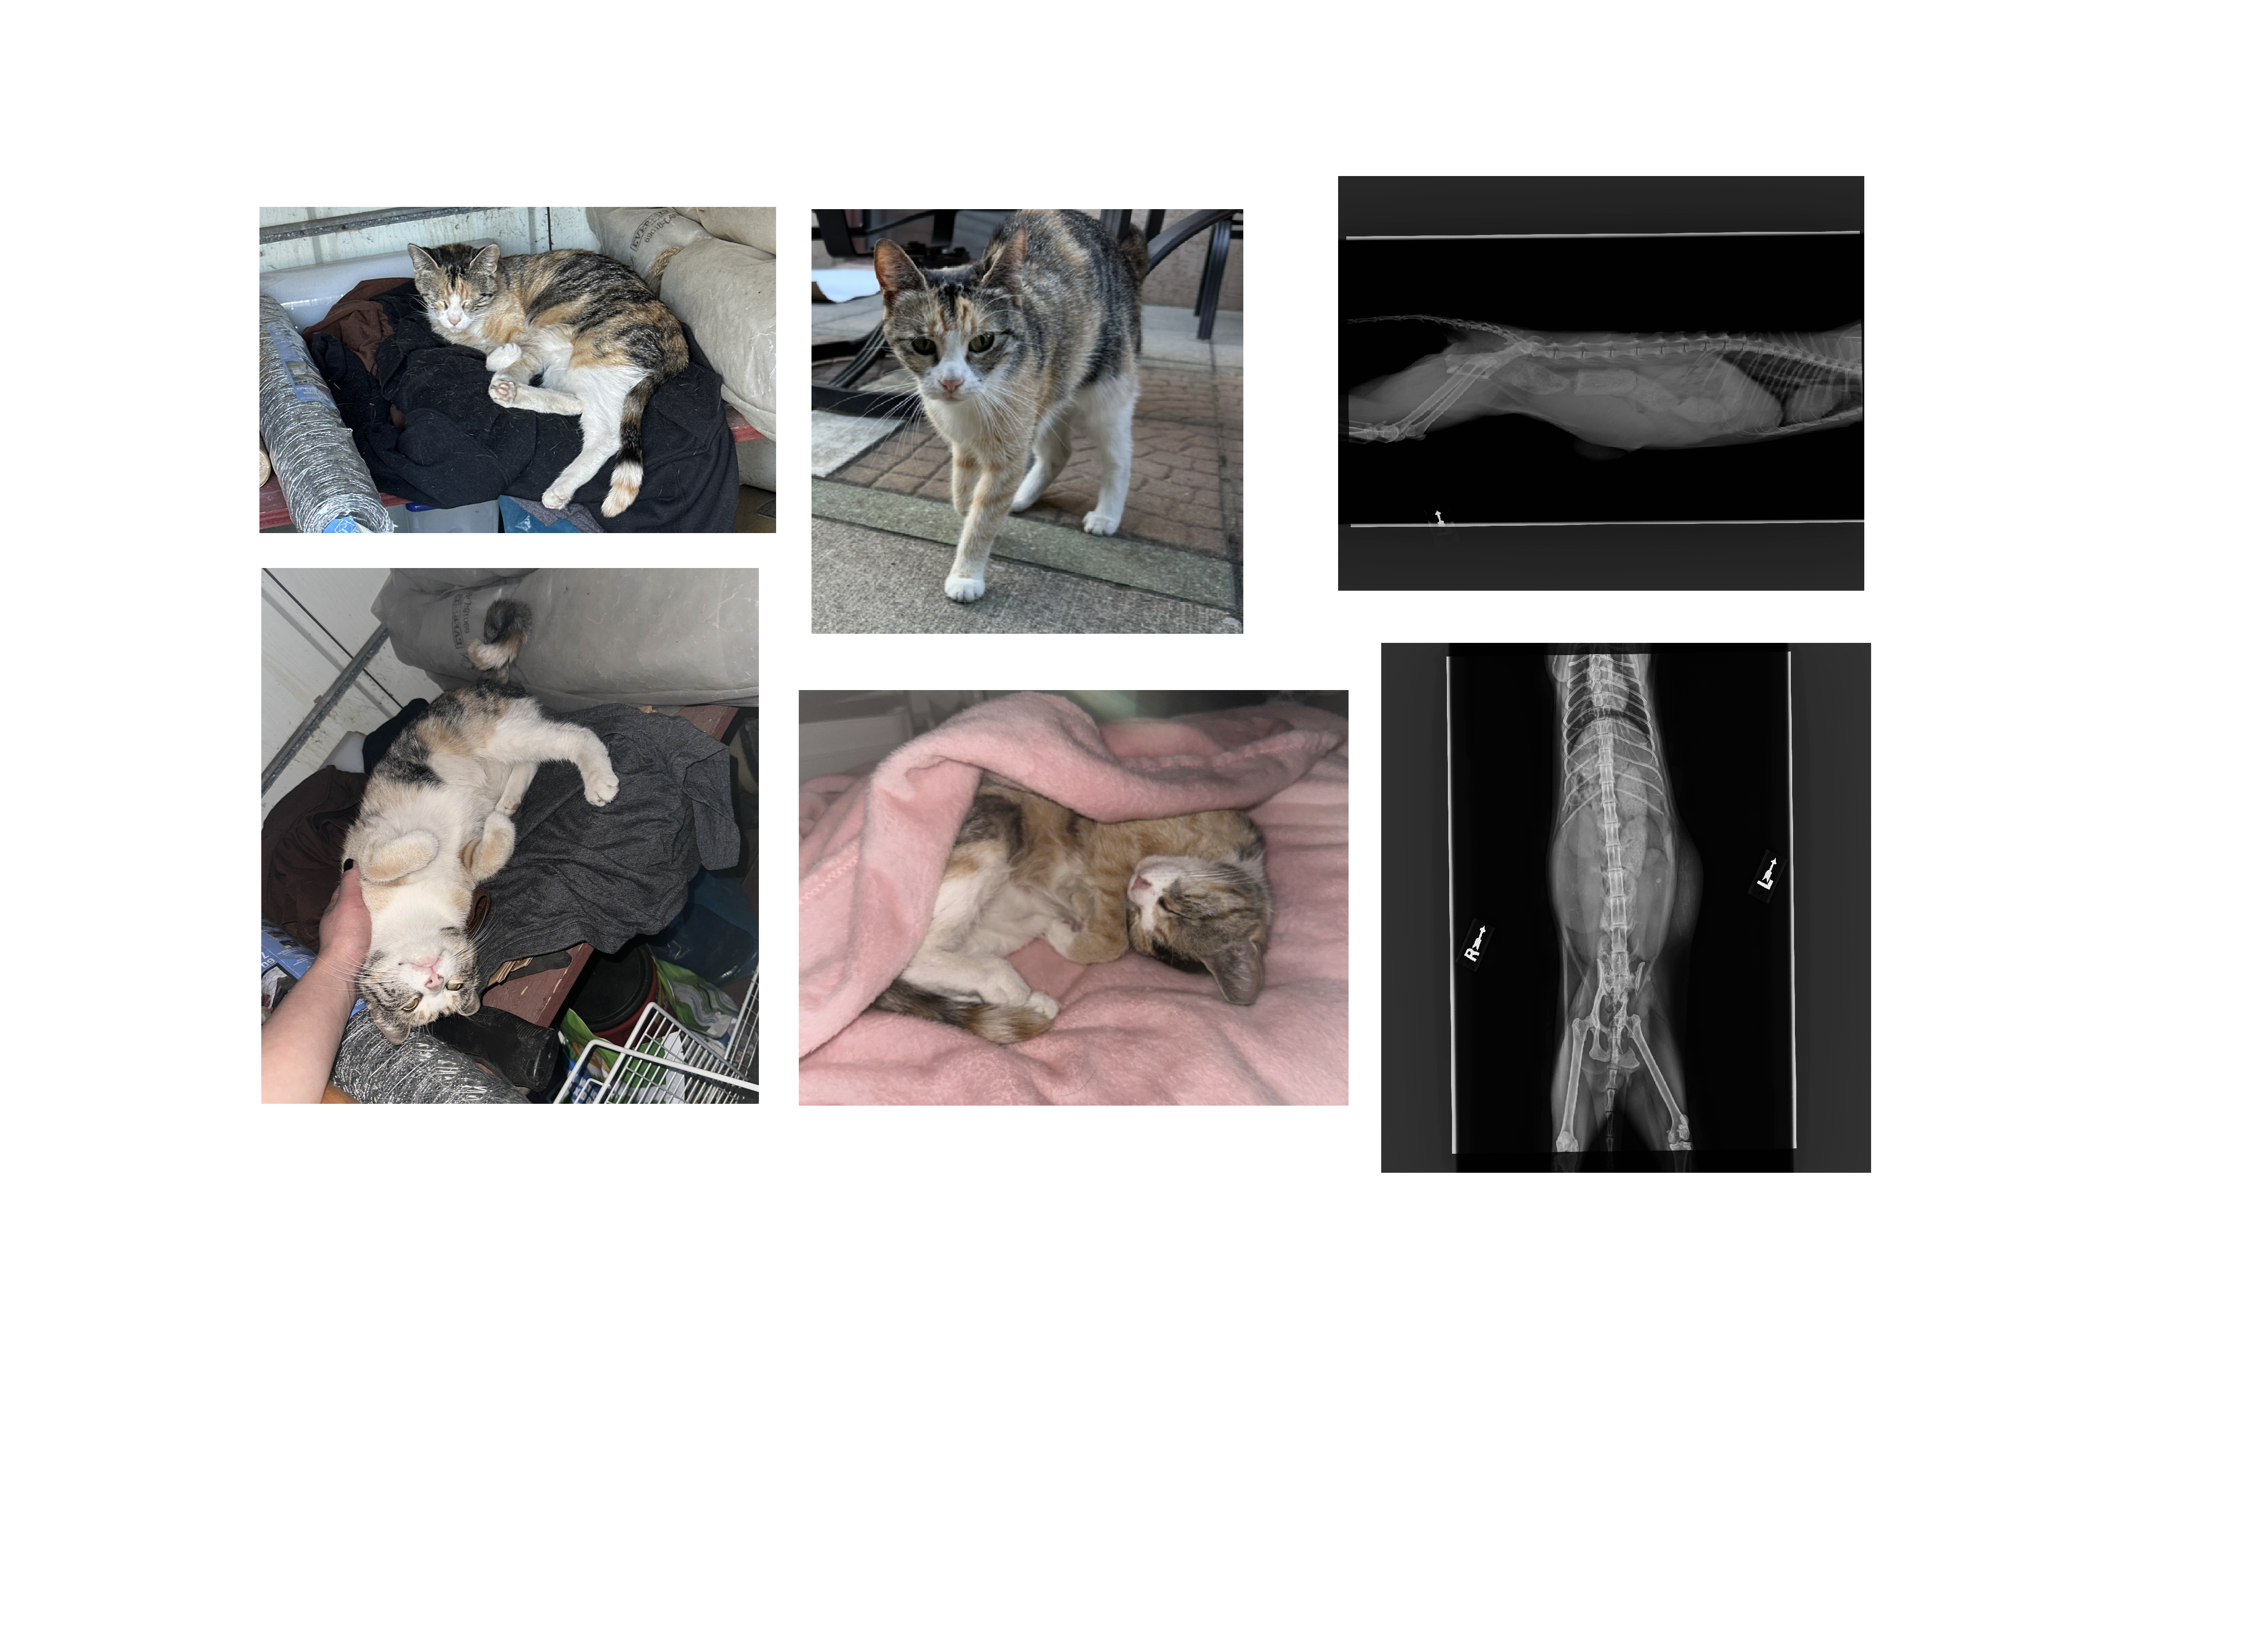

Hi everyone, my name is Rachael. I had recently decided to take on this sweet stray baby who showed up giving us a cry for food and help, we fed her outside and she was always greeting us with her tail up. About a week ago I noticed she had wanted to come inside and I decided to allow her to have a safe place to stay and took her in, and I've since grown incredibly attached to her. Being horribly bad at names, one of my dear friends named her Sampo after a video game character and that has since stuck. The first night she was inside, she jumped up on the bed, curled up right infront of my face and fell asleep. It was only a short while of falling inlove with her, but the impact she had on me was more than I can describe before I discovered devastating news.

During the first vet visit I had asked if she might be pregnant, and noticed she walked strangely to which the first vet told me she was perfectly healthy and was not likely pregnant. Upon seeing another doctor and emergency vet, it's been uncovered that she was hit by a car, pregnant with three kittens, and severely constipated (this has now turned into obstipation as I type)

She is loving, friendly, and incredibly trusting. I'm trying to do everything I can for her. She has an incredible will to live it and I want to do everything that I can to give her what she deserves.